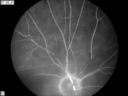

CRAO411 viewsCRAO in OD of a 37 yr old Male, Transit Phase

CRAO352 viewsCRAO in OD Late Phase of FA

CRAO386 viewsCRAO in OD Tranisit Phase of FA

CRAO340 viewsCRAO in OD Tranisit Phase of FA